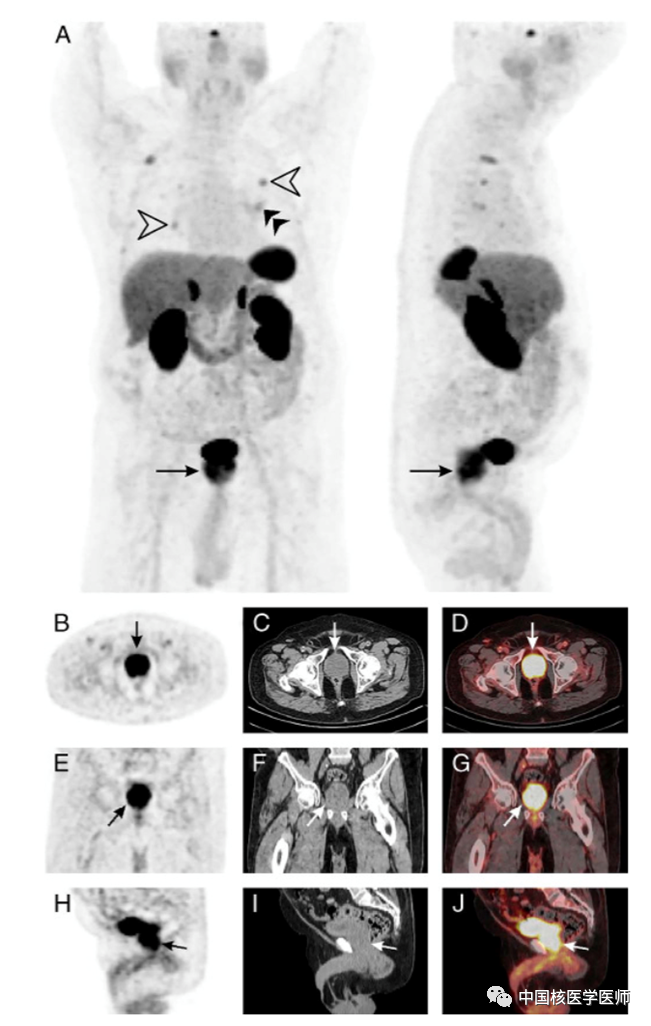

摘要:一名79歲的男性患有類癌綜合征并發現雙側肺結節,肺結節活檢證實為分化良好的神經內分泌腫瘤。68Ga-DOTATATE PET/CT顯像提示雙肺多發結節、左側肺門淋巴結明顯攝取顯像劑,此外還發現前列腺彌漫性攝取68Ga-DOTATATE。回顧患者的病史發現該患者的前列腺特異性抗原水平升高。進一步的前列腺活檢提示良性前列腺增生,未見前列腺癌細胞。

圖 1. 一名79歲的男性患有類癌綜合征并發現雙側肺結節,肺結節活檢證實為分化良好的神經內分泌腫瘤。隨后患者接受了68Ga-DOTATATE PET/CT顯像評估。MIP圖顯示明顯攝取68Ga-DOTATATE的雙側多個肺結節(A,白色箭頭)、左肺門淋巴結(A,雙黑色箭頭)和前列腺(A,黑色箭頭)。前列腺增大,橫斷位測量約大小約為5.1 X 4.1 cm(A,黑色箭頭;B,黑色箭頭;C,白色箭頭;D,白色箭頭;E,黑色箭頭;F,白色箭頭;G,白色箭頭;H,黑色箭頭;I,白色箭頭;J,白色箭頭)。前列腺呈彌漫性攝取68Ga-DOTATATE,經體重校正后的SUVmax為11.5(A,黑色箭頭;B,黑色箭頭;D,白色箭頭;E,黑色箭頭;G,白色箭頭;H,黑色箭頭;J,白色箭頭)。回顧該患者的病史,發現其前列腺特異性抗原水平升高。進一步的前列腺活檢提示為良性前列腺增生,未見前列腺癌細胞。

研究報道,在病愈患者中,有正常的前列腺攝取68Ga-DOTATATE的報道,但攝取程度多為彌漫性輕度攝取。體外研究已經證實正常和增生的前列腺基質平滑肌中存在生長抑素受體 (SSTR) 的表達。神經內分泌腫瘤患者的前列腺、空腸、胰腺、回腸和唾液腺可有中度 68Ga-DOTATATE攝取,SUV在3.5-7的范圍內。在正常前列腺組織中發現非常低水平的 SSTR 表達,而在肥大和增生的前列腺組織中SSTR表達則相對較高。目前我們報道的良性前列腺增生患者的高SUVmax值的病例與之前的研究結果一致,該研究表明增生和肥大的前列腺中68Ga-DOTATATE PET顯像SUVmax值更高。前列腺癌比正常前列腺組織的SSTR表達高很多。伴有前列腺癌的神經內分泌腫瘤患者SUVmax最高。在晚期前列腺癌患者中也觀察到了骨轉移和盆腔轉移淋巴結攝取68Ga-DOTATATE,特別是在去勢抵抗性前列腺癌患者中,據報道骨和淋巴結轉移中68Ga-DOTATATE攝取增加。此外,應注意具有神經內分泌分化的前列腺癌,其表達的是SSTR而不是前列腺特異性膜抗原。在這種情況下,使用68Ga-DOTANOC PET/CT和18F-FDG PET/CT比68Ga-PSMA PET/CT對患者腫瘤進行分期、再分期和指導管理可能更合適